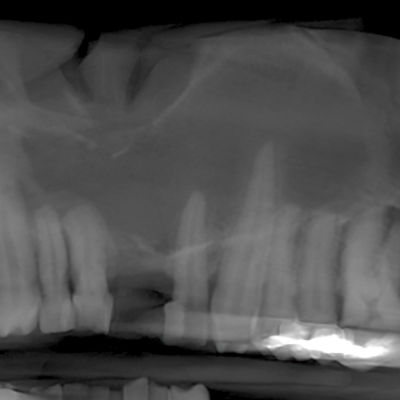

A 6-year-old girl was referred to the oral surgeon by her dentist for a radiographic lesion located in the right mandible.

A 59-year-old woman was referred to the oral surgeon by her dentist because of a “lesion” on the right mandible that was discovered in a panoramic x-ray.

A 9-year-old girl was referred to the oral surgeon by her family dentist because of a “lesion” on her right mandible.

A 66-year-old man presented to the oral surgeon, referred by his dentist, because of a lesion that was noted on his anterior mandible in a panoramic radiograph.

A 12-year-old boy presented to the oral surgeon because of an anterior mandibular lesion noted on a panoramic radiograph.

A 30-year-old woman was referred to the oral surgeon by her dentist because of a “bone lesion” noted on a panoramic film.

An 18-year-old boy was referred to the oral surgeon by his dentist concerning an unusual finding that was discovered during a recent recall exam.

A 29-year-old woman was referred to the oral surgeon by her dentist because of a radiopaque lesion in the posterior right mandible.